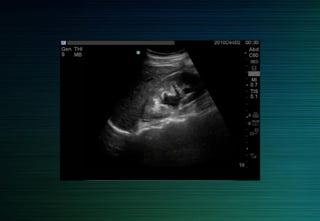

Rein droit

Abord latéral ou antérolatéral

Foie: fenêtre acoustique

(antérolatéral)

Incidence intercostale: pôle supérieur